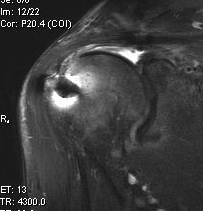

Large / Massive Cuff Tear

Large Subscapularis tear